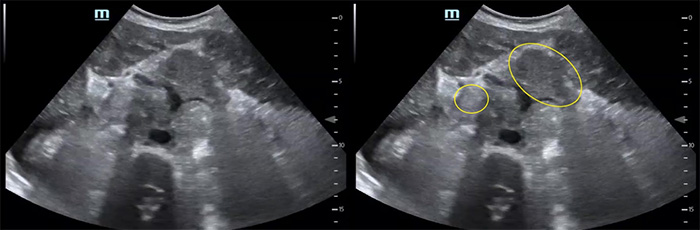

- Ascites (Fig. 6)

- Ascites is a common finding in many disease entities however in the patient with HIV from a TB endemic area, it is highly suggestive of TB.

- With or without fibrinous debris: OR 2.221

- Without fibrinous stranding: PPV= 73% NPV = 33%18

- With fibrinous stranding: PPV = 86% NPV= 41%18

Figure 7. Fibrinous ascites in pelvis sagittal view

Figure 8. RUQ free fluid with fibrinous stranding and hyperechoic liver lesions

- Free abdominal fluid will have irregular sharp edges as the fluid surrounds loops of bowel, while fluid contained in the bladder should have smooth rounded edges (Figure 7).